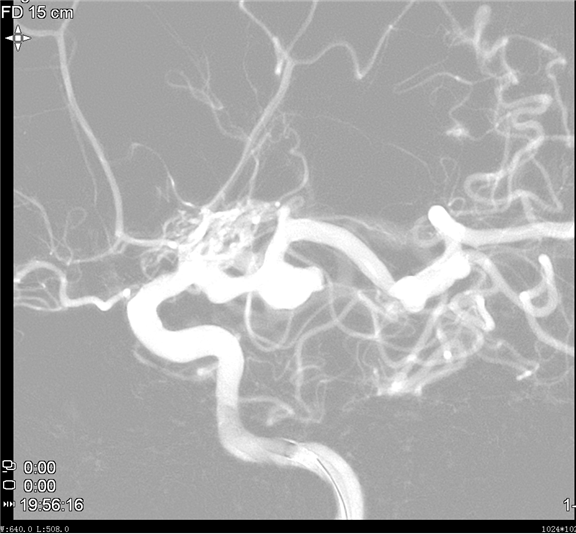

温柔守候——当烟雾病遇上宽颈动脉瘤

患者基本信息女性,51岁,主诉头痛1天入院治疗。初步诊断1、烟雾病;2、动脉瘤破裂蛛网膜下腔出血;3、胚胎型大脑后动脉动脉瘤术前影像学检查动脉瘤位置、侧别:右侧大脑后动脉P1段测量大小:5.93mm×7.04mm×6.44mm瘤颈测量:4.50mm子瘤大小:2.44mm×2.38mm×2.07mm 此病例动脉瘤瘤颈宽,母动脉瘤体顶端有一个子瘤,顶端血流导入子瘤,造成子瘤破裂出血风险高。 术前思考1、该动脉瘤位于右侧大脑后动脉P1段,且患者系烟雾病,大...